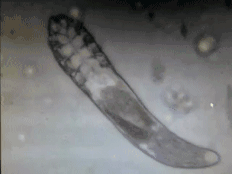

今天丽格君为你揪出痘痘元凶——蠕形螨,俗称毛囊虫 。 和尘螨那种自营生计,不依附于人类也可生存下去的螨虫不一样,这种螨虫寄生于人体皮肤毛囊,皮肤的某些疾病就与它有关 。

(显微镜下的毛囊虫GIF)